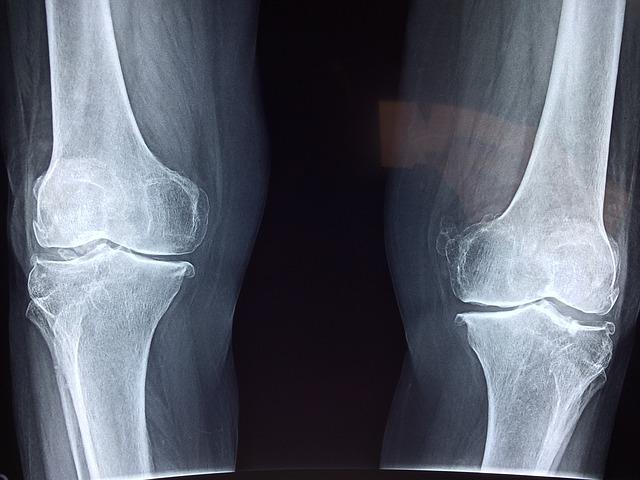

V kůži vytvářejí tenká vlákna kolagenu (tzv. fibrily) prostorovou síť, která drží tvar a pružnost; v kostech se kolagen I mineralizuje a dává jim tažnou pevnost; v chrupavce je zásadní kolagen II, který tlumí nárazy v kloubech. Porozumět, „kde jaký typ je“, pomáhá pochopit, proč různé tkáně stárnou a hojí se jinak.1